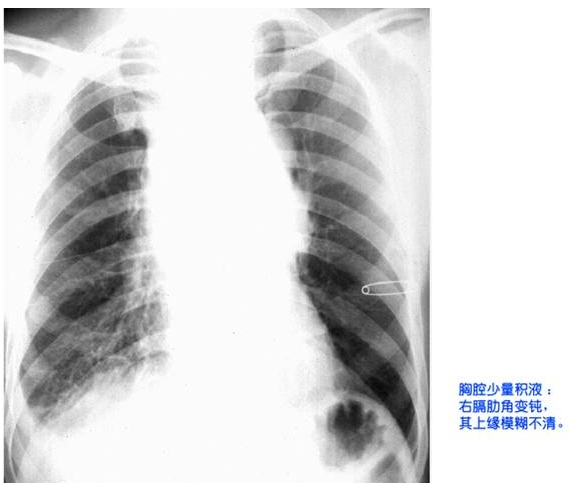

照片名称:胸腔少量积液